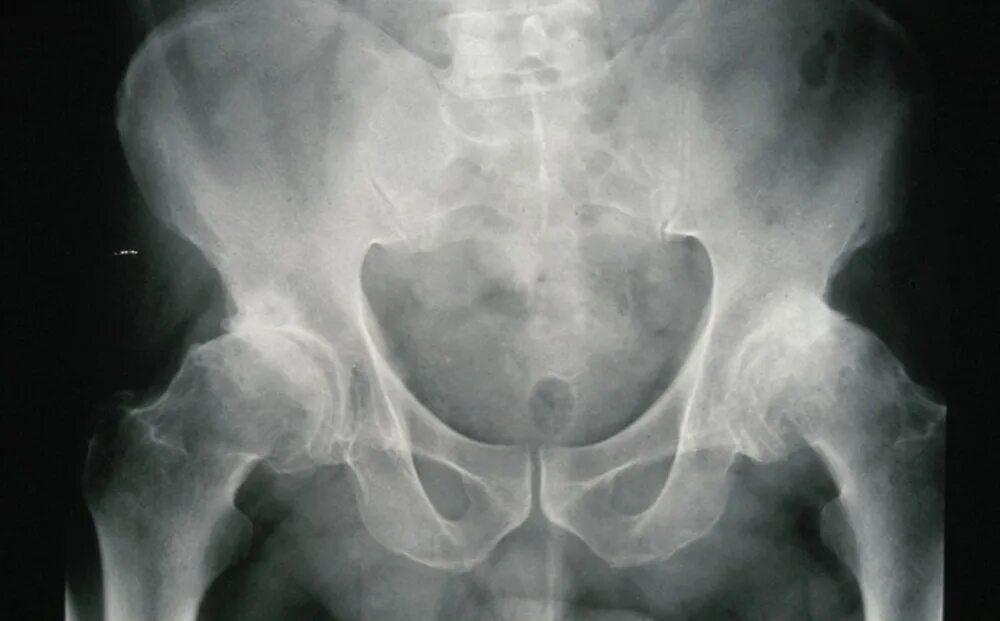

Склероз вертлужной впадины